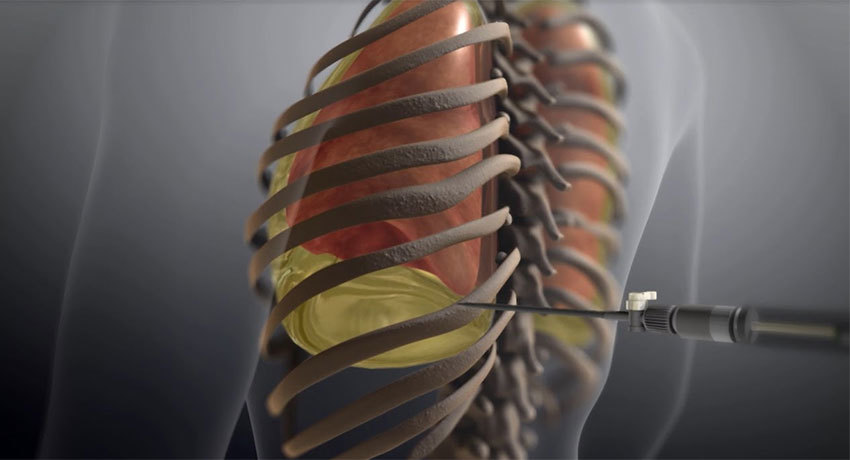

Торакоцентез и плевроцентез – это 2 названия метода удаления жидкости из плевральной области. В ходе плевроцентеза врач прокалывает грудную стенку иглой или специальным инструментом (троакаром), а затем удаляет скопившийся в плевральной полости гной или жидкость. Врачи Юсуповской больницы выполняют плевроцентез как в диагностических целях, с целью определения причины появления жидкости в плевральной полости, так и с лечебной целью, для удаления экссудата или гноя.

Торакоцентез, или плевроцентез, – это инвазивная процедура, в ходе которой в плевральную полость через прокол в грудной стенке вводится катетер, через который удаляется скопившаяся жидкость, а также гной или воздух.

После обеззараживания места пункции и введения анестезии с помощью специального инструмента (троакара), представляющего собой металлическую трубку и вставленную в нее трехгранную иглу, в грудной стенке делается прокол. Как правило, в 6-м, 7-м и 8-м межреберном промежутке в средней или задней подмышечной линии. Наиболее подходящее в конкретном случае место определяют с помощью УЗИ.

Торакоцентез, или плевральная пункция, представляет собой сравнительно несложное хирургическое вмешательство на грудной клетке. Это прокол стенки грудной полости, который осуществляется для того, чтобы врач мог получить доступ к плевральной полости пациента.

Прокол производится с использованием местного обезболивания. Пациент находится в положении сидя, а его рука с соответствующей стороны заведена за голову. Кожу на месте будущего прокола обрабатывают антисептиком, после чего хирург быстрым и точным движением прокалывает кожу и подкожно-жировую клетчатку с помощью специальной пункционной иглы. При этом ее острие двигается по краю ребра: это предотвращает риск повреждения кровеносных сосудов и межреберных нервов.

Манипуляции предшествует определение уровня жидкости, который отмечается на коже соответствующими метками. После предварительного обследования выбирается место для прокола: для извлечения жидкости – между седьмым и восьмым ребром по линии от подмышки до края лопатки, для воздуха – во втором межреберье ниже ключицы.

Место прокола обрабатывается антисептическими препаратами и послойно обезболивается. Прокол осуществляется иглой, которая при попадании в плевральную область меняется на пункционную. С ее помощью воздух или жидкость выпускаются, после чего происходит обработка зоны воздействия лекарственными препаратами из группы антисептиков для предотвращения осложнений.